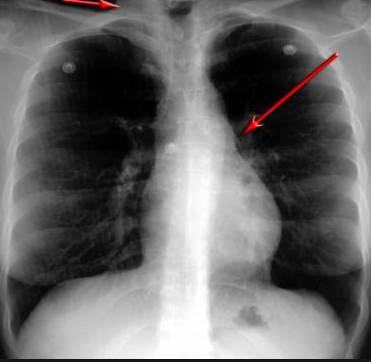

并且,因為呼吸系統(tǒng)結構復雜,在體檢時醫(yī)生很難通過一種檢測手段,判定早期患者的病情。

把整個肺部看得清清楚楚!

使用這臺掃描儀,將直接把器官變成3D圖形!細微的毛細血管,幾毫米大的肺泡和支氣管,都將能看的一清二楚!

你的每一個氣泡,每一段支氣管,哪兒有病變都清清楚楚的將展示在醫(yī)生面前!

也就是說在一切都還沒開始惡化前,把這些有問題的器官組織都暴露的一清二楚:

空氣是如何進入到肺部,氧氣是如何到血液,任何微小的變化都將曝露在醫(yī)生面前!更清晰的圖像,更細節(jié)的變化!

沒有這項新技術,醫(yī)生在做體檢的時候,很難通過一種測試斷定一個人是否有呼吸系統(tǒng)疾病。

可是現(xiàn)在他們不但能看到整個肺部的3維結構圖。還能看到空氣進入人體后的所有微小變動!